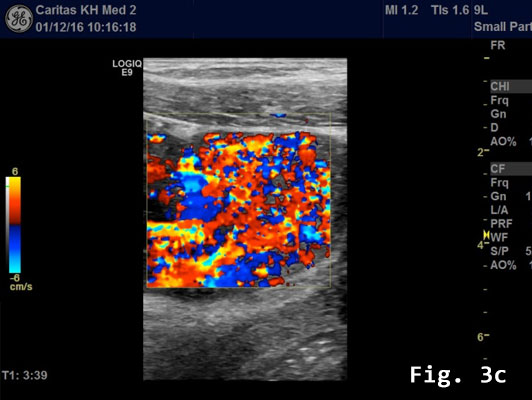

Contrast enhanced ultrasound (CEUS) showed a rapidly and heterogeneously enhancing lesion during the arterial and venous phases [Figure 3]. Contrast enhanced colour Doppler ultra-sound confirmed the finding.

![Endometriosis infiltrating the sigmoid colon</br> [May 2017]](http://s834315022.websitehome.co.uk/wp-content/uploads/2020/11/cotm_may2017_fig3c.jpg)